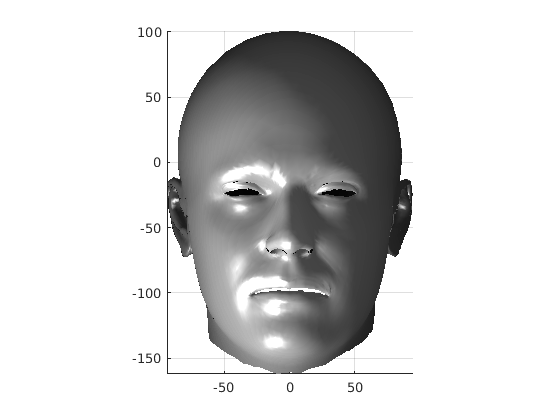

Fig. 9 shows examples of the fitted model (trained on FRGC data) on the first four subjects in our Headspace training set. Note that the mean of the landmarks in the sparse model is centred on the orgin, and so the scan data is moved towards that and becomes frontal in pose. We note that other researchers [28] have used 3D landmark localisation to find the head, but often this only includes landmarks that are relatively easy to localise, namely inner eye corners and nose. Localising more landmarks over a wider facial area has a number of advantage in terms of cropping, pose normalisation and global 3D template warping, all of which are described later.

The template mesh is then warped in a global affine sense, as shown in Fig. 27 to minimise the least-squares error between the two sets of landmarks, when the head scan is fixed in its canonical poose. After this initial stage, landmarks and pseudo-landmarks are used in the same way as any other mesh vertex, as they are potentially noisy, as seen in earlier results analysis. This contrasts with Amberg et al’s [11] approach where the influence of landmarks is gradually faded out.

Following this, OSNR ICP iterates over a set of decreasing mesh stiffnesses (typically 10), until the registration between the template and the scan is below some error or a maximum number of iterations is reached. Figure 28 shows a selection of template warp results. The template appears to be accurately warped onto the scan, at least in the normal direction of the surfaces, it is not possible to see error tangential to the surface. Furthermore, we have noted errors on some scans on the ears. To improve these we need a method of automatically landmarking the ears, which is an area for further work.

The first two modes of head variation are shown in figures 29 and 30. These include the cranial height / facial angle mode and the (almost) pure size mode, as seen in the sagittal profile model.